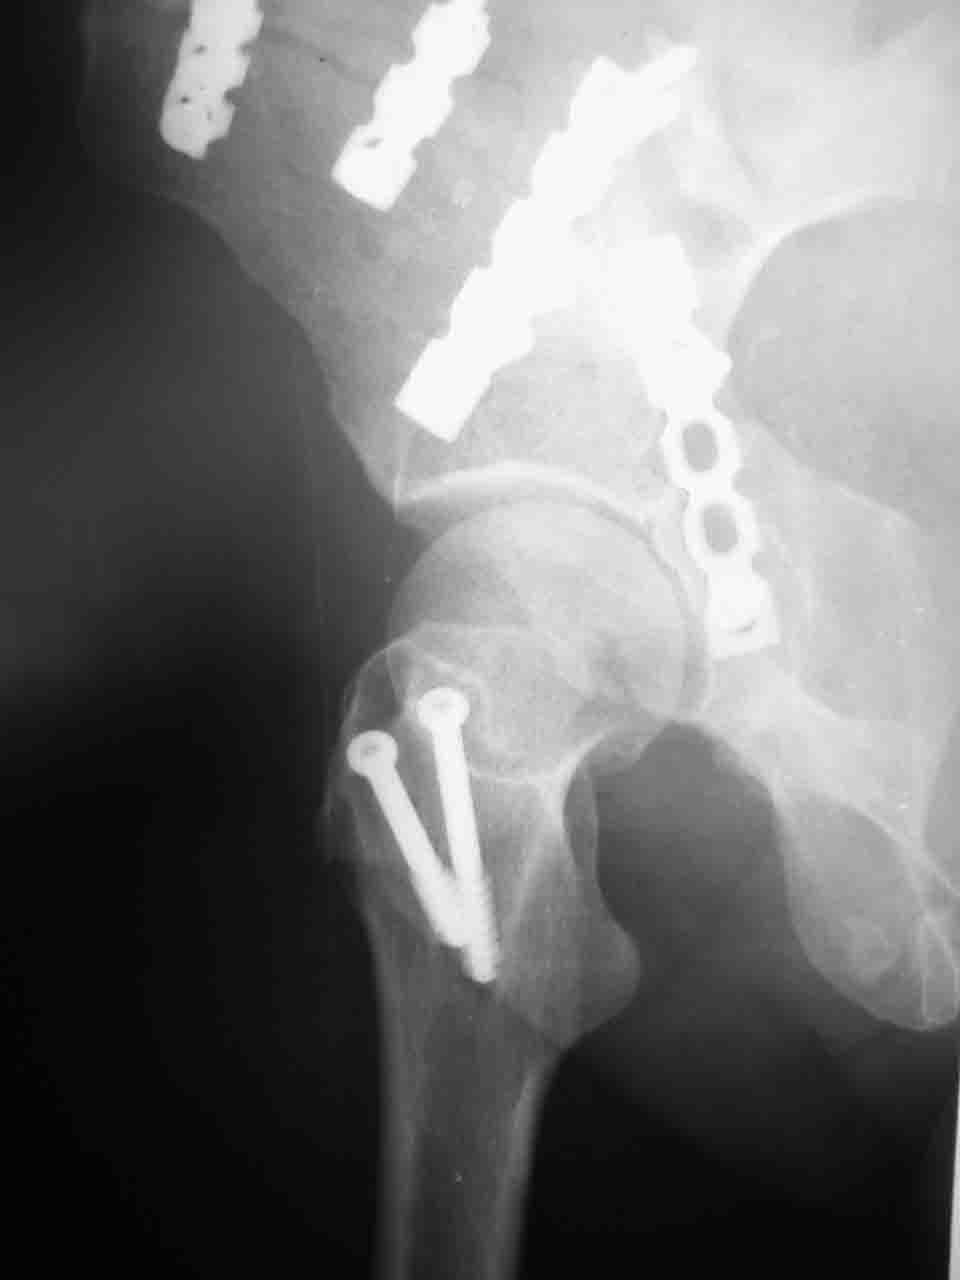

Вопрос доступа к вертлужной впадине при остеосинтезе задача не простая. Конечно, у Летурнеля и Тайла всё давно описано, нам остается только брать на вооружение. Но сами понимаете, что не бывает двух одинаковых ситуаций, поэтому в каждом случае вопрос решается сугубо индивидуально. Наша главная цель - восстановить анатомию с нанесением минимальной дополнительной травмы тазобедреннному суставу, думаю с этим никто не поспорит. Расширенный илиофеморальный доступ уж слишком травматичен (как сказал один коллега "таз лежит отдельно, больной отдельно").Стоит ли делать из пациента анатомический препарат для того чтобы легче ориентироваться. Да и нужно ли собирать всю "мозаику"? Мы применяли при таких операциях своеобразную операционную хитрость - сначала устраняли грубое смещение крыла под гребнем с фиксацией так называемой "плавающей" пластиной (временно фиксированной на двух винтах)- доступ или продлевали боковой, или делали небольшой дополнительный разрез над гребнем. Это позволяло устранить грубое смещение и захождение отломков тела повздошной кости, что значительно облегчало репозицию и остеосинтез впадины над сводом. Основное внимание конечно же уделяли нагружаемому задне-верхнему отделу. Сообщите ваш адрес, пришлю схемы и рентгенограммы.

С уважением, Алексей.